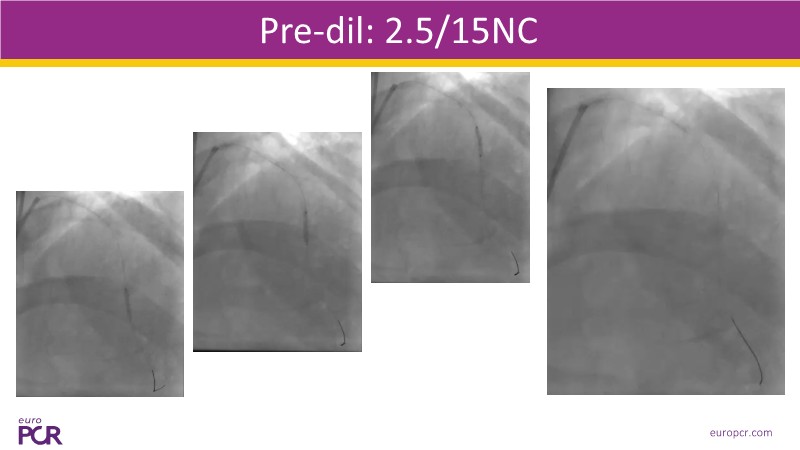

This EuroPCR 2025 session provides a comprehensive overview of drug-eluting balloons (DEBs) and their growing role in percutaneous coronary intervention (PCI). Gain a clear understanding of the clinical evidence and rationale supporting DEBs, including how these devices minimize metal implantation and effectively treat both standard and complex coronary lesions. The session highlights the mechanistic advantages of drug selection and sustained drug release technologies, with a focus on the SELUTION SLR DEB. Clinical updates include the LOVE-DEB study advocating a DEB-first approach in large vessel coronary artery disease, real-world performance data from the Malaysian registry, and practical case examples illustrating the transition to DEB-based PCI in clinical practice.